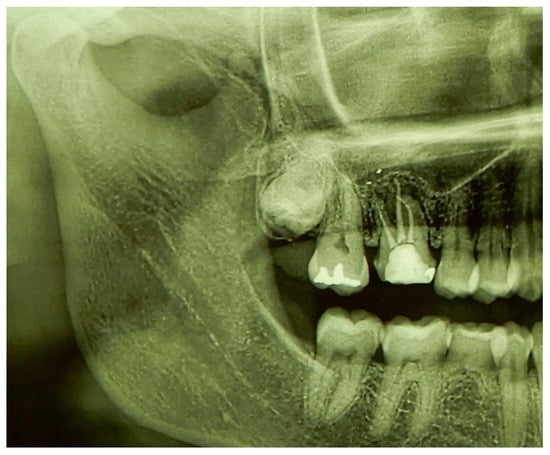

3.2. Case Report